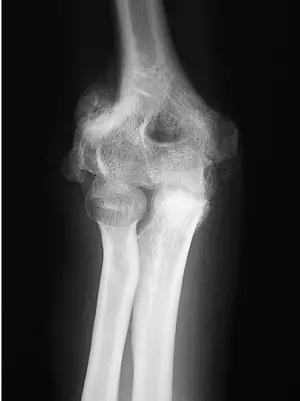

- 解剖位置:提供的 X 光影像顯示的是一個手肘關節 (Elbow Joint),而非題目文字敘述中的「膝部」。我們可以清晰辨認出肱骨遠端 (distal humerus)、尺骨鷹嘴突 (olecranon of ulna) 以及橈骨頭 (radial head) 的結構。

- 病理特徵:在關節周圍的軟組織中,可見大量不規則、雲霧狀及高密度的異常骨化組織 (Ectopic bone formation)。這些骨化組織包覆在關節周圍,形成了骨橋 (bony bridging),嚴重限制了關節的活動空間。這是典型的異位骨化症 (Heterotopic Ossification) 影像表現。